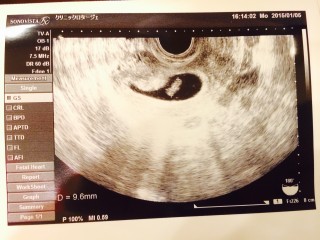

• おなまえcana

• ねんれい30

• 妊娠週5w3d

4w5dの時は何も見えず…今回5w3dで初めて胎嚢(9.6mm)を確認できました! 診察後、少し茶おりが出て不安でしたが、落ち着きました。 次は明後日…6w2dに病院に行く予定です。心拍確認出来ますように…